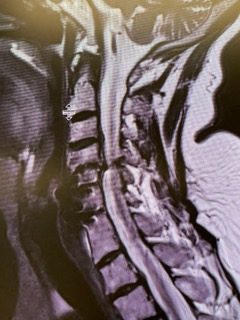

This is a 57-year-old woman with new onset memory problems and gait difficulty. MRI demonstrated a 3 cm tumor in the pineal region, most consistent with a meningioma growing inferiorly off the right tentorium.

Figure 1: Preop post contrast axial MRIs demonstrating a pineal region meningioma with hydrocephalus.

The tumor was causing compression of the upper brainstem and hydrocephalus. The tumor was removed by Dr. Michael Brisman using a right occipital / transtentorial approach.